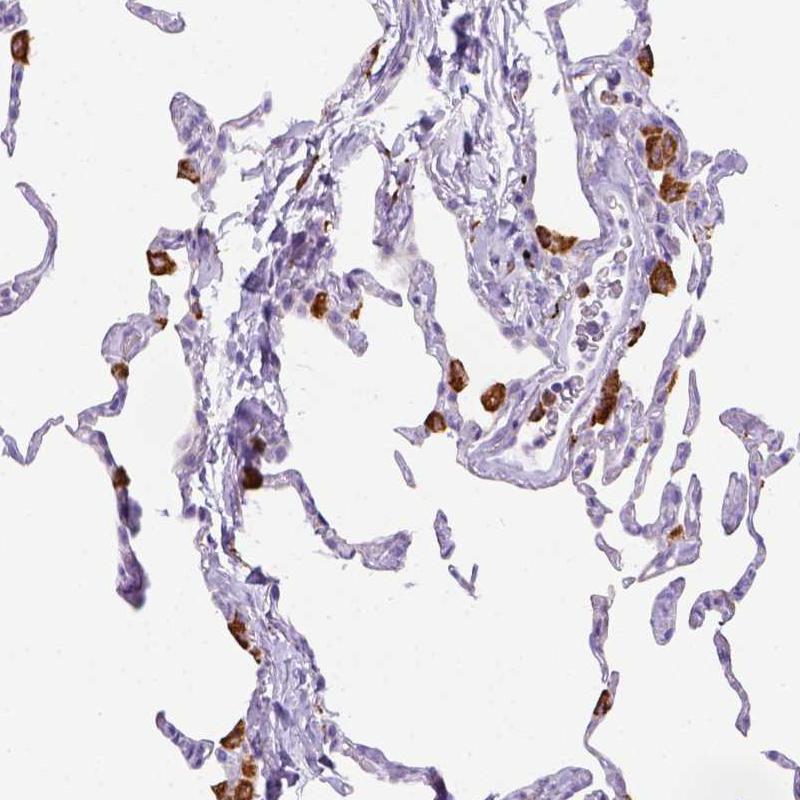

Immunohistochemical staining of human lung shows strong cytoplasmic positivity in macrophages.